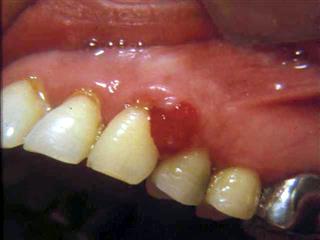

En décembre 1995, ce même patient vient consulter pour une hyperplasie gingivale entre 46 et 45, masse bourgeonnante sensible au contact. Il y a un tassement alimentaire entre ces deux dents du fait d’une carie mésiale de la dent de 6 ans. La biopsie confirme la présence d’une épulis inflammatoire, sans éléments suspects. L’exérèses est pratiquée. Ainsi ce jeune patient a présenté à 13 ans d’intervalle deux tumeurs bénignes de la cavité buccale, pourtant assez rares, surtout le pulpome. Peut-on, dans ce cas, occulter le rôle d’un « terrain » prédisposant ? Car toutes les irritations gingivales ne se terminent pas par une épulis. Sur le plan morphologique, ce jeune patient est manifestement « carbonique ».